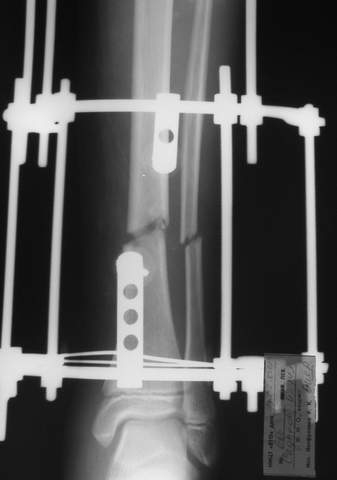

В аттачте № 3 - один из примеров полукольцевого аппарат...

Это уже я баловался.

Итог? Работы больше (по времени и

интраоп "подгонке"), срастается также, а особого преимущества по сравнению с

"чиста" кольцевым (вес, удобство ношения и пр.) - я, по крайней мере,

не нашел.

Теперь не балуюсь.

Может быть зря?

МТ мы используем, конечно, не только на голени. В прилагаемом примере у парня при поступлении была наружная ротация 40 гр. и "полумертвый" коленный сустав. Можно был бы, конечно, до конца использовать полную компоновку. Но для того он и есть метод выбора.